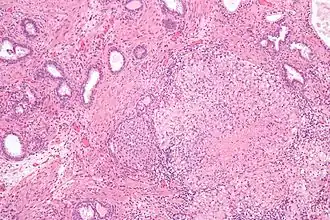

![]() Гранулёматозный простатит вследствие лечения рака мочевого пузыря вакциной БЦЖ | |

При гистологическом исследовании биоптата ткани предстательной железы больного гранулёматозным простатитом обнаруживается значительная деструкция ацинарных протоков предстательной железы, инфильтрация предстательной железы эпителиоидными клетками, гигантскими клетками, лимфоцитами, плазматическими клетками и гистиоцитами, а также плотный фиброз (разрастание соединительной ткани и замещение ткани предстательной железы соединительной тканью).